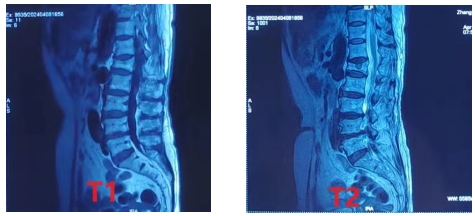

腰椎MR: